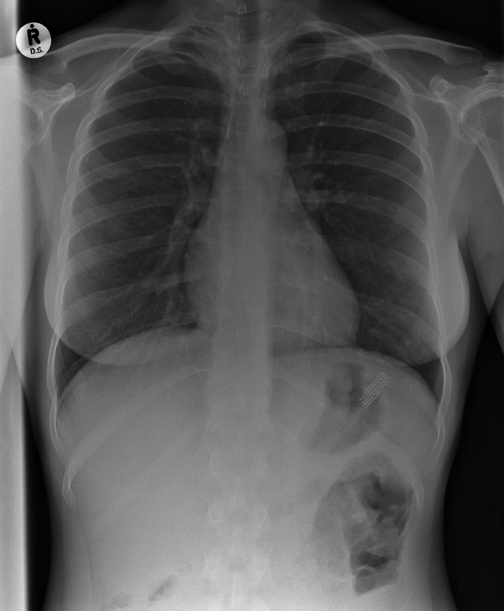

8) ¿Y qué opinas de ésta? un estadounidense de 21 años sobrevivió de milagro luego de que la motosierra con la que trabajaba cortando árboles se le “enrollara” en su pecho.

Allegheny Health Network | The Telegraph